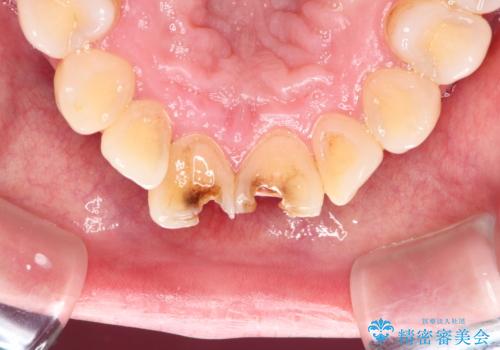

- 白い詰め物が急に外れたとの事で来院された患者様です。前歯にデンタルフロスも出来ず気になっていたとの事でした。

神経の検査をした所、問題ないので神経を残して被せ物の処置を行いました。